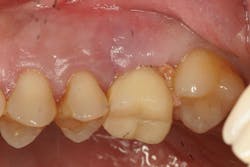

The most critical aspect of any implant system is the interface between the implant fixture and its surrounding bone (figures 1-5). Integration between the fixture and its surrounding bone is the foundation of modern implant dentistry. There is little we can do to modulate bone healing, but we can modify the implant fixture itself.

Figures 1-5: Figures 1 through 4 illustrate, respectively, a seven-year follow-up visit and a three-year follow-up visit of two different implant systems. Implant No. 22 (figure 5) shows peri-implant radiolucency following functional loading, indicating fibroencapsulation and loss of integration into bone, necessitating removal.